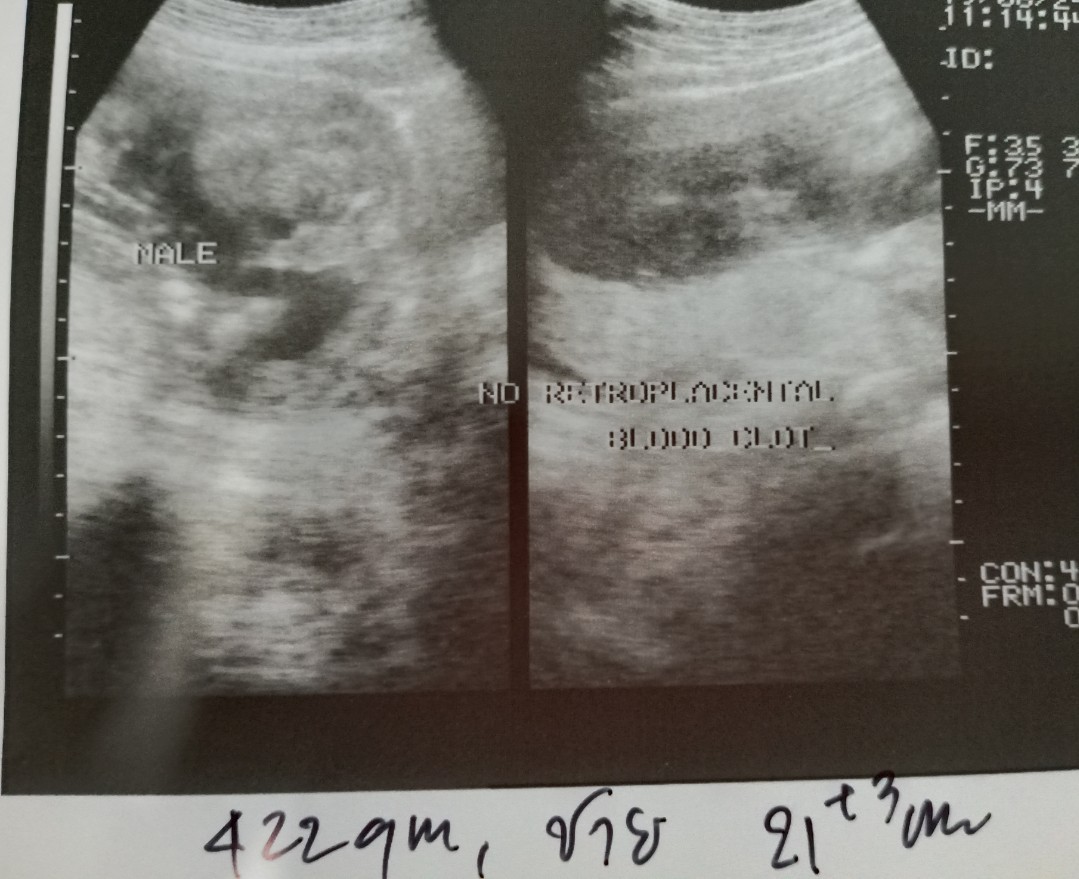

21week